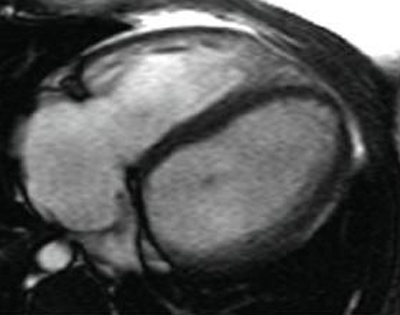

Ressonância nuclear magnética (RNM) em um paciente com regurgitação pulmonar após reparo de tetralogia de Fallot. O paciente tem ventrículo direito restritivo e a RNM mostra volume ventricular direito reduzido

De: Chaturvedi RR, Redington AN. Heart. 2007 Jul;93(7):880-9; usado com permissão